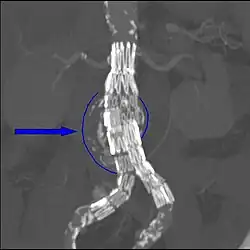

Biomechanical AAA rupture risk prediction -

An axial contrast-enhanced CT scan demonstrating an abdominal aortic aneurysm of 4.8 by 3.8 cm -